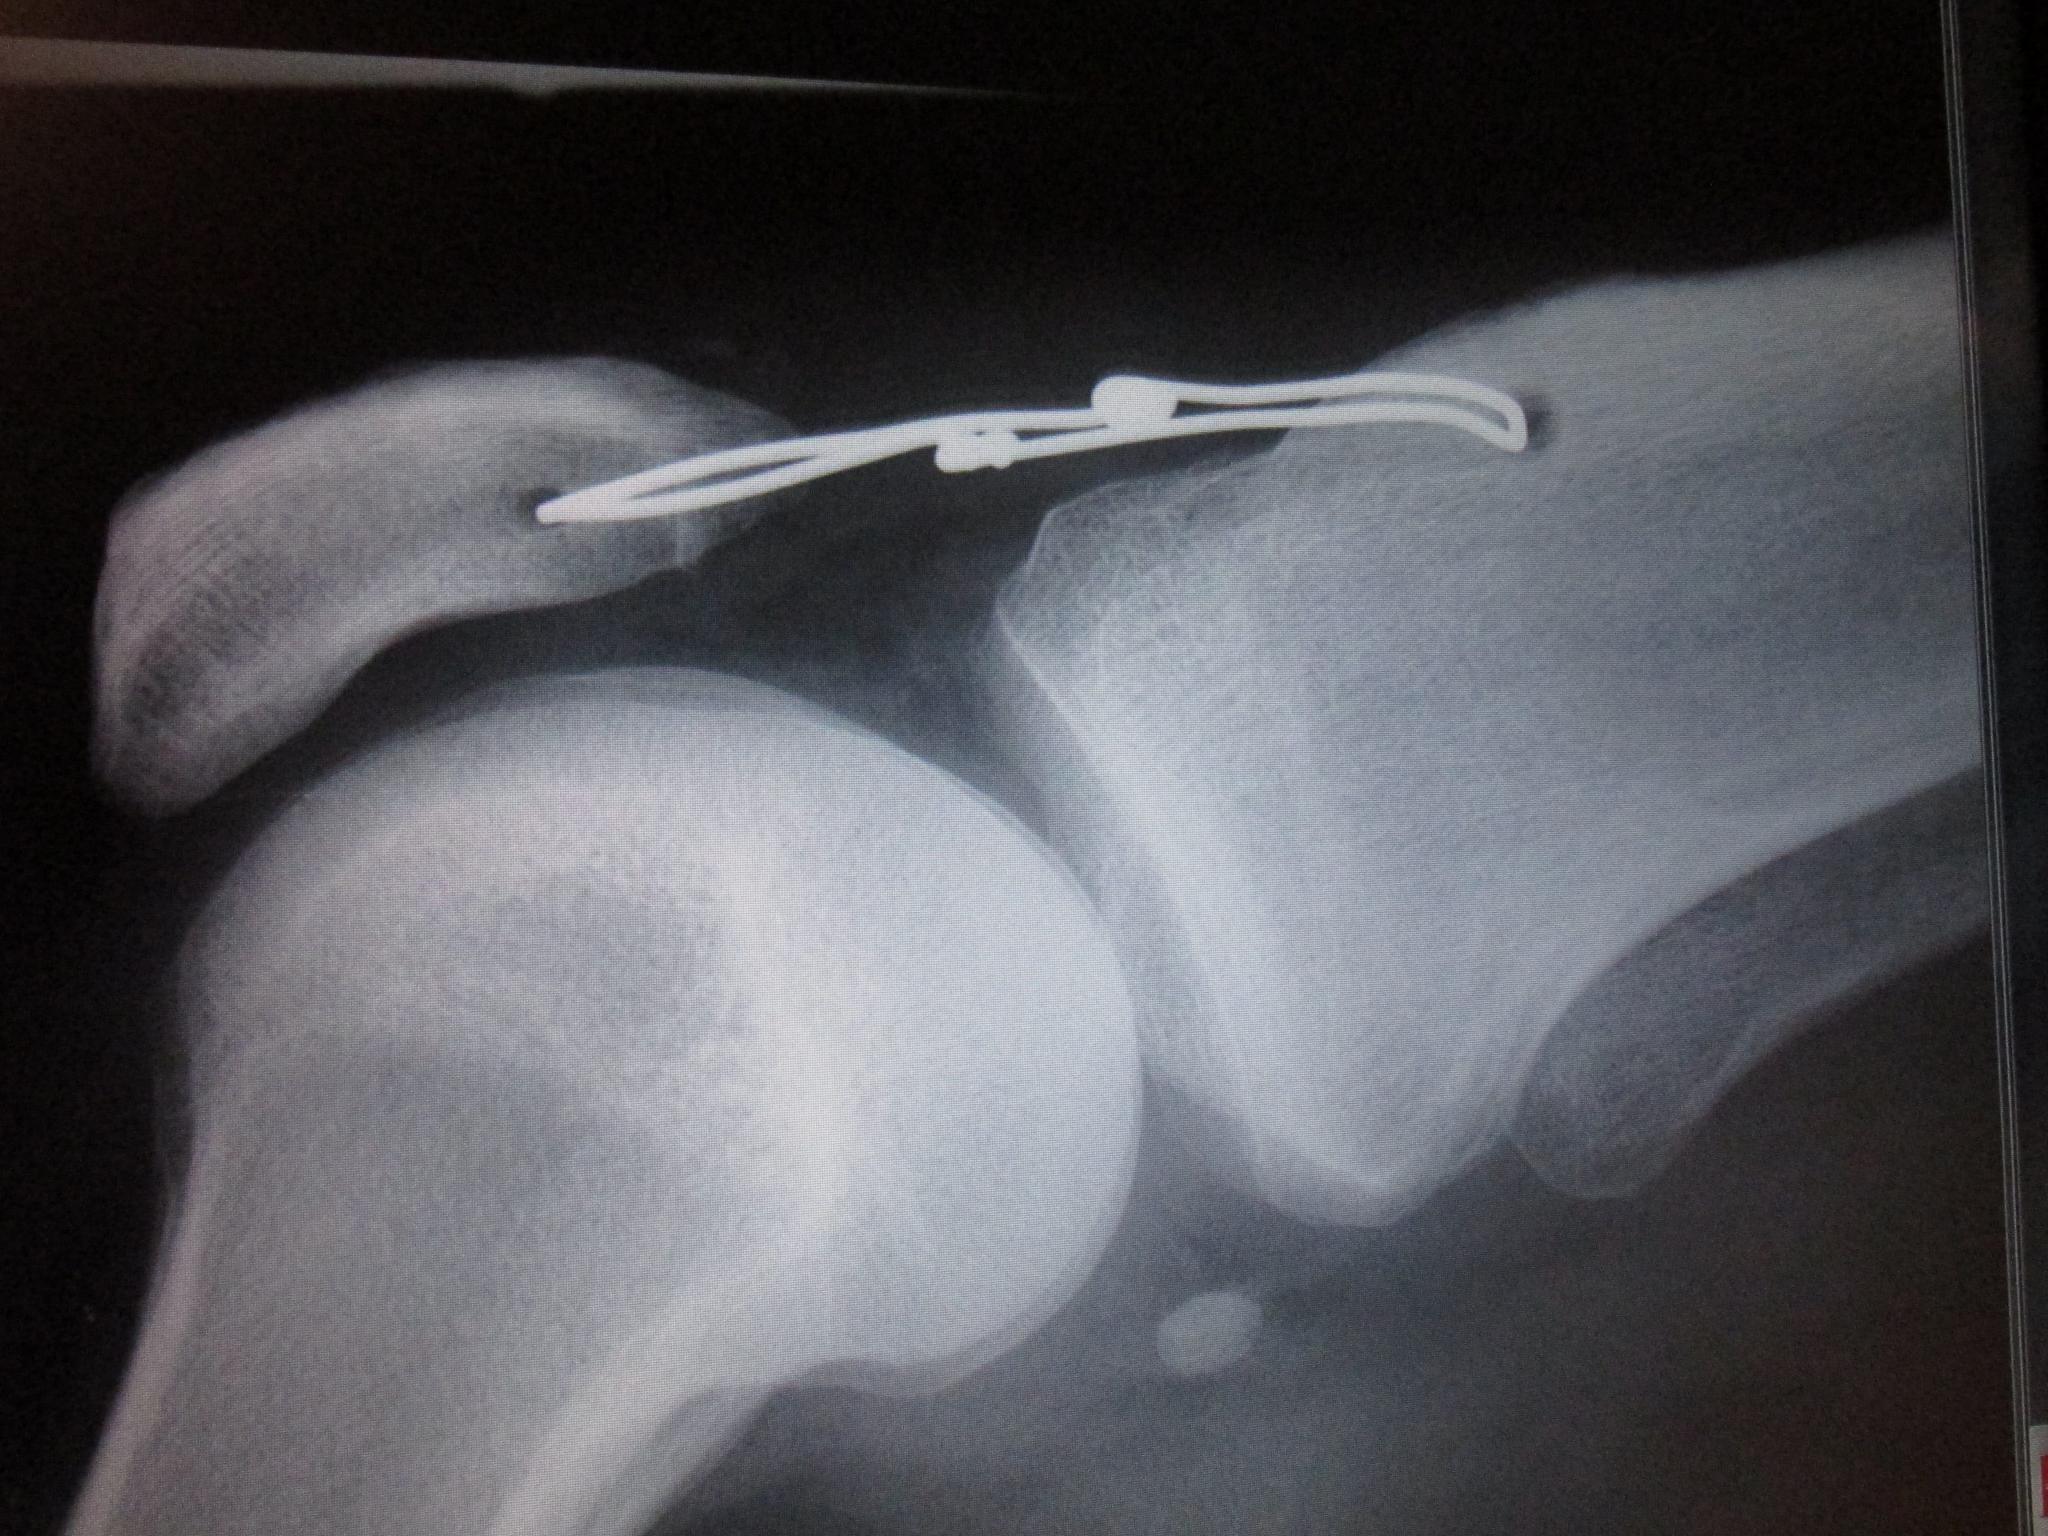

der Draht ist auch net gerissen, siehe Föterli :shifty:

hat Sie aber auch schön gemacht, die Drahtenden verdrillt, Frauenhände eben.... :clap:

voraussichtlich am 27.1. Wird der Draht gezogen und so kann auch irgendwann die Saison losgehn.....